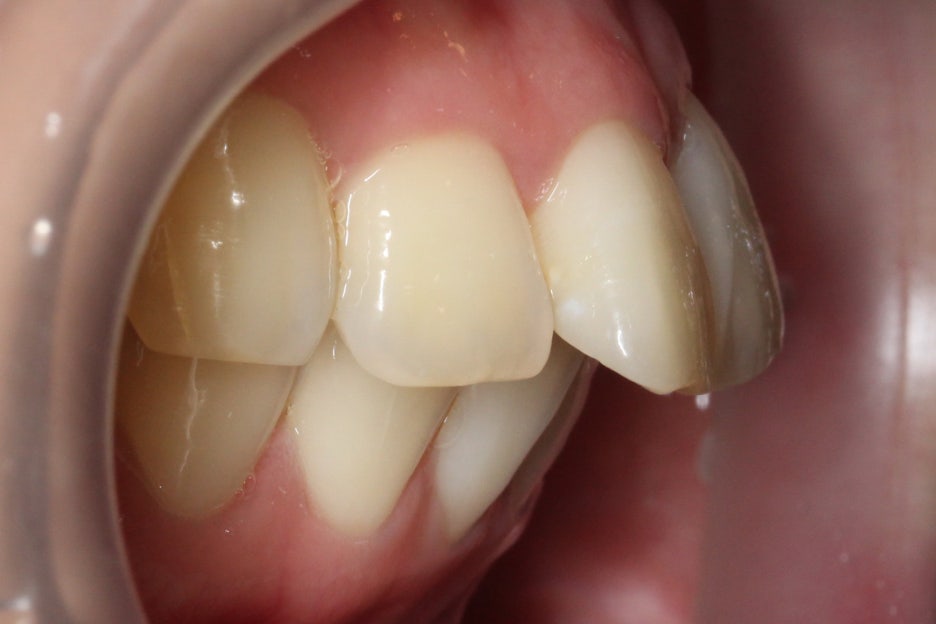

전치에서 구치까지 이어지는

협측 사진을 보시면 중절치의

튀어나온 모습을 명확하게

확인할 수 있습니다.

위의 case에서는 upper teeth만

부분적으로 교정하기 때문에

하악의 교합과 배열까지

고려하기는 어렵지만

최대한 윗니에 맞추어

이상적인 치열을 만들어 보려고 합니다.